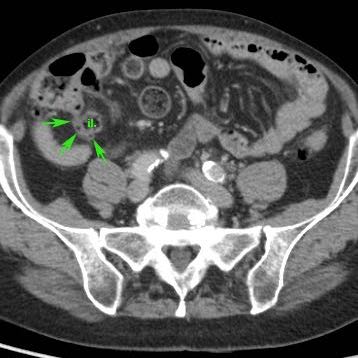

Ở bệnh nhân này, siêu âm cho thấy lượng lớn mô mỡ viêm (*) và hồi tràng dày thành, biểu hiện quá trình bao bọc thành công tình trạng thủng (sắp xảy ra) của ruột thừa (mũi tên).

Lưu ý sỏi phân vôi hóa (mũi tên trên CT) trong ruột thừa ở mức cao hơn.

Quá trình “bao bọc” này càng kéo dài, việc cắt ruột thừa sẽ càng khó khăn hơn.

Vấn đề nan giải này được thảo luận trong chương “khối ruột thừa”.